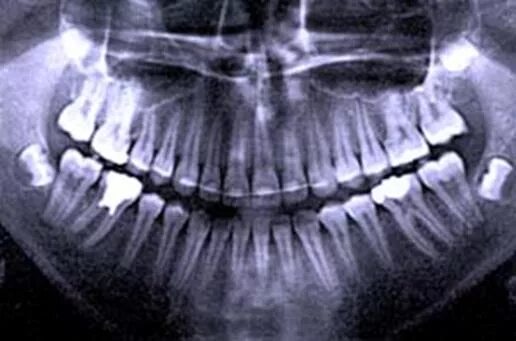

Снимок ротовой полости